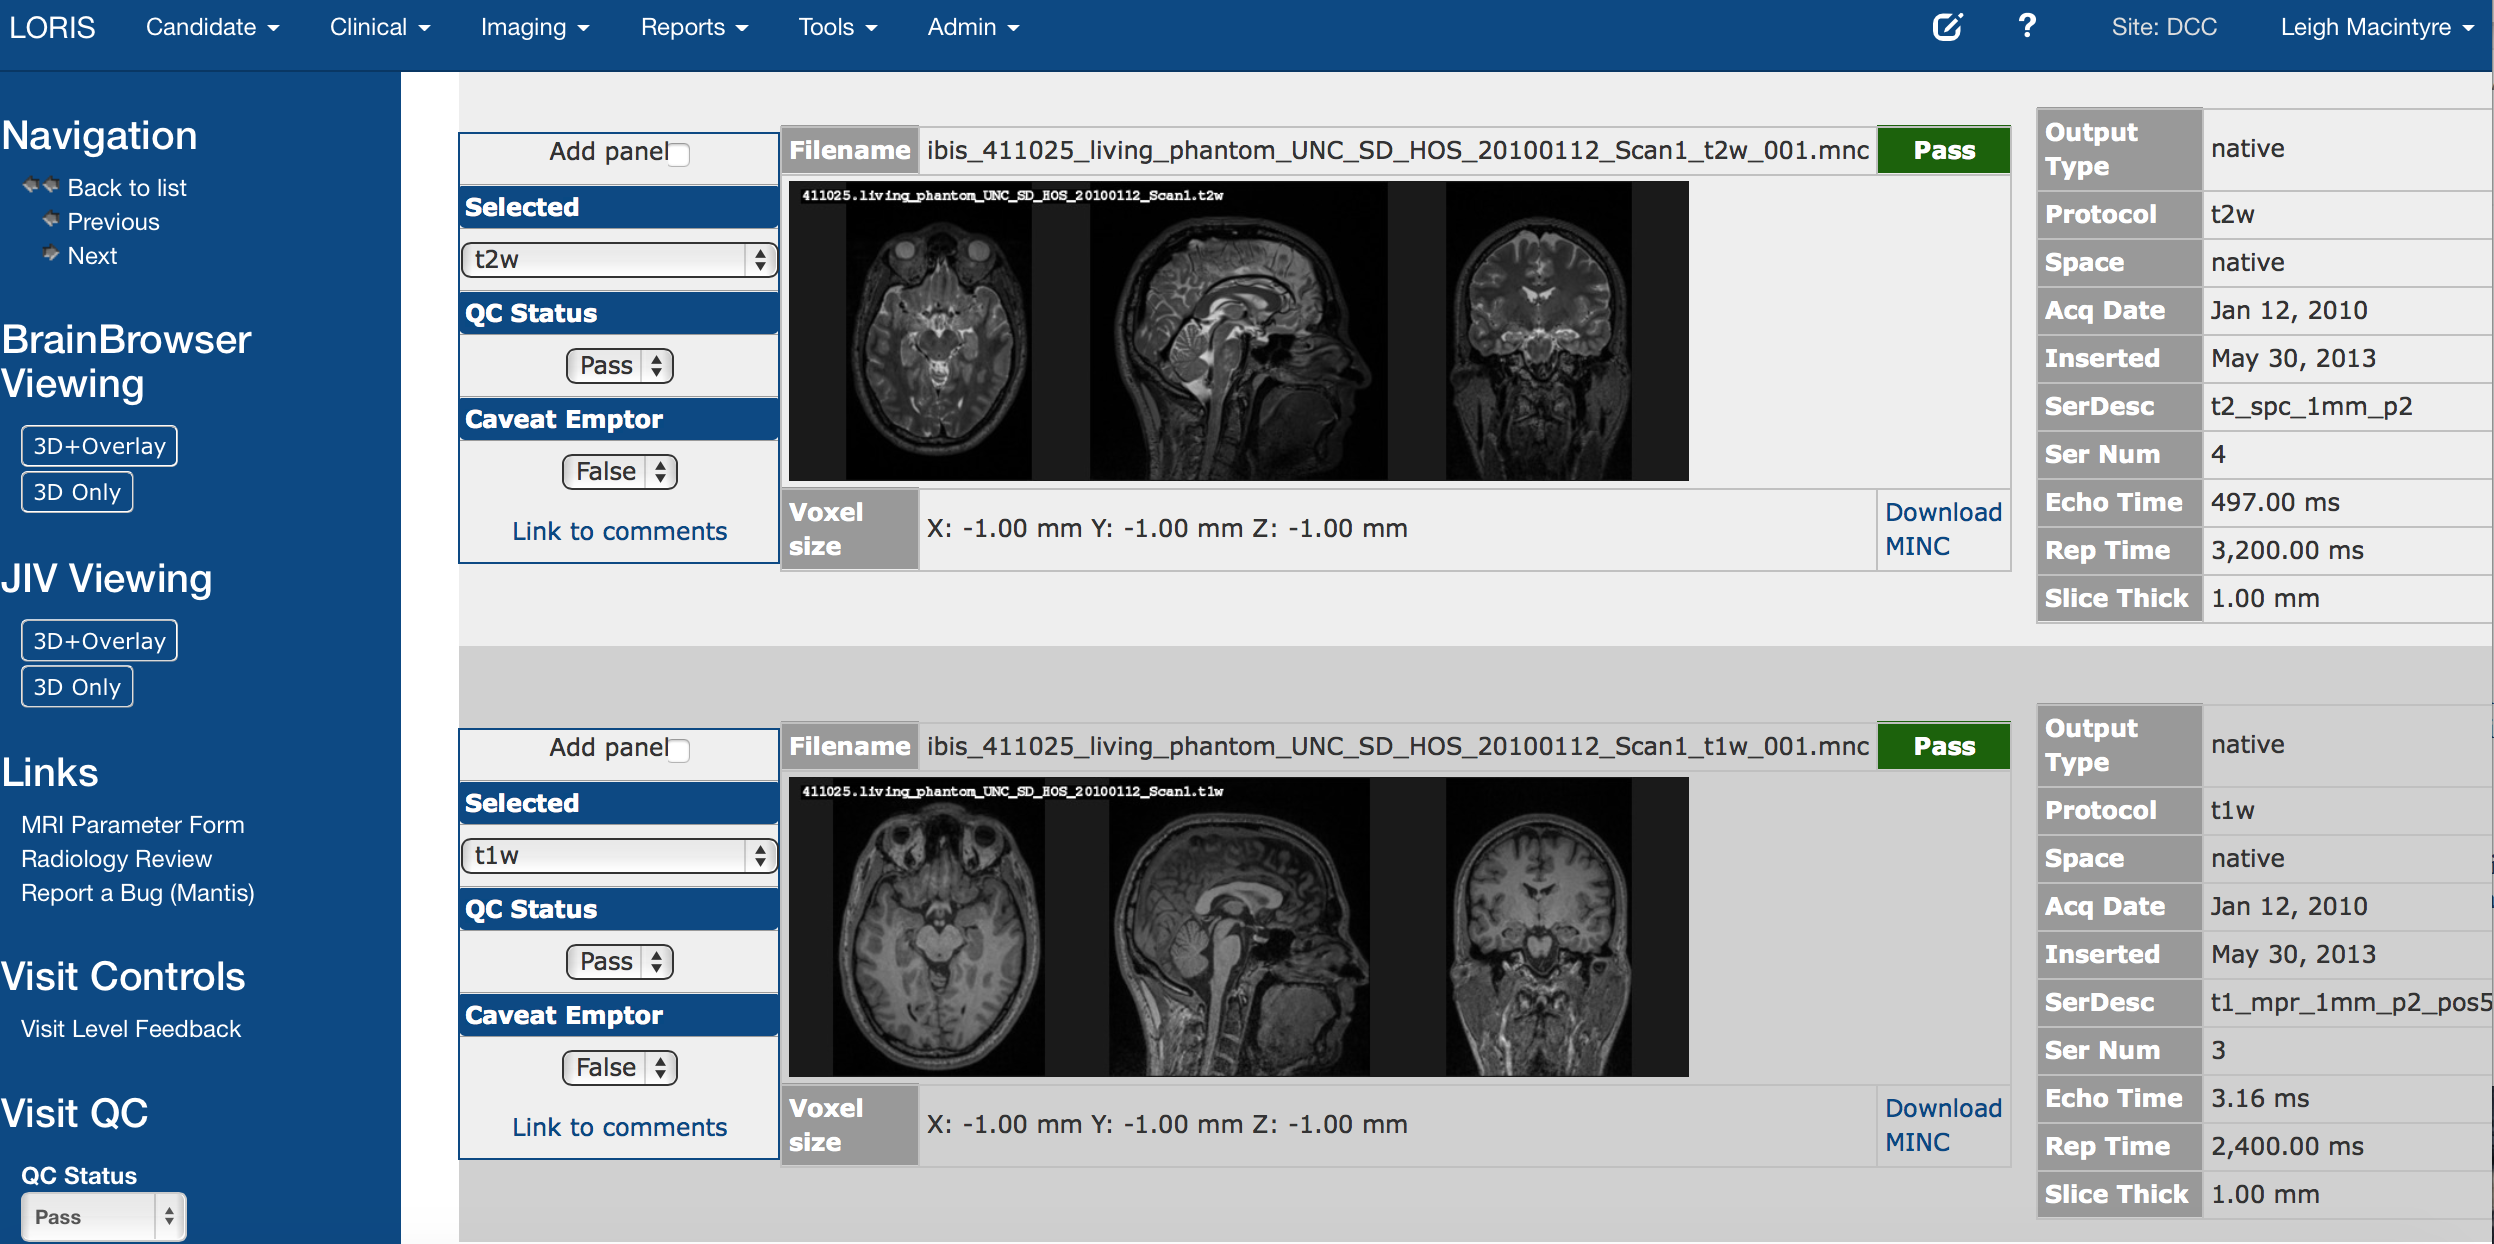

Imaging Browser

Imaging Quality Control

Imaging Browser, BrainBrowser3. Quality Control:

Radiological Review Module, DCC MRIData Querying